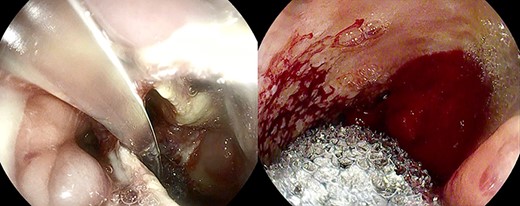

Anastomotic dehiscence was conservatively treated by EVAC therapy, placing the Esosponge in pleural space via an overtube (Fig. 2).

EVAC uses the main principle of negative pressure wound therapy by decreasing bacterial contamination and local edema while promoting perfusion and granulation tissue formation. The sponge can be placed in either an intraluminal or an intracavitary position across an internal fistula opening, using the overtube with a designated pusher. In our case, the sponge was always set inside the cavity because of the large size of the collection.